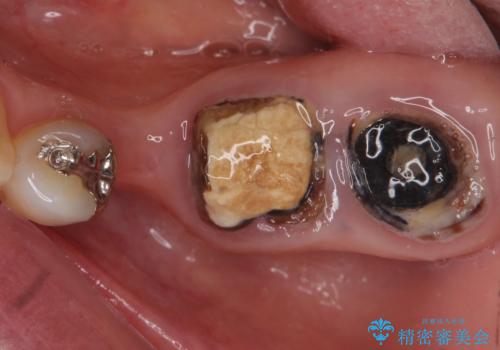

- 奥歯のブリッジの被せ物がとれてしまったとの主訴で来院された患者様です。

奥歯2本は虫歯により残っている健全歯質が少ないため、保存が難しい状態でした。

抜歯してインプラントを提案したところ、「どうしても抜きたくないので残してほしい」と強くご希望されました。

長期的な予後を保証できないことをご了承頂いた上で、歯根分割術、骨外科手術により歯の保存を試みました。

虫歯を丁寧に除去した後に歯根を分割し、骨を削合して健全歯質を露出させる骨外科手術を行いました。